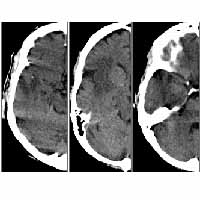

Existing “content-based” image retrieval systems depend on general visual properties such as color and texture to classify diverse, two-dimensional (2D) images. These general visual cues, however, often fail to be effective discriminators for image sets taken within a single domain, where images have subtle, domain-specific differences. Furthermore, these visual properties are not necessarily the true content of an image, nor do they have a proven correspondence to image semantics, i.e. the meaning of an image. Databases composed of (3D volumetric or 2D) images and their collateral information in a particular medical domain form simple, semantically well-defined training sets, where the semantics of each image is the pathology indicated by that image (for example, normal, hemorrhage, stroke or tumor in neuroimages, or normal v. cancer in microscopic images). The goal of our research is to

Our approach is a principled method firmly rooted in Bayes decision theory. Techniques in memory-based learning, feature selection and statistical regression are adopted in our system to achieve classification-driven, semantic based image analysis, indexing and retrieval.